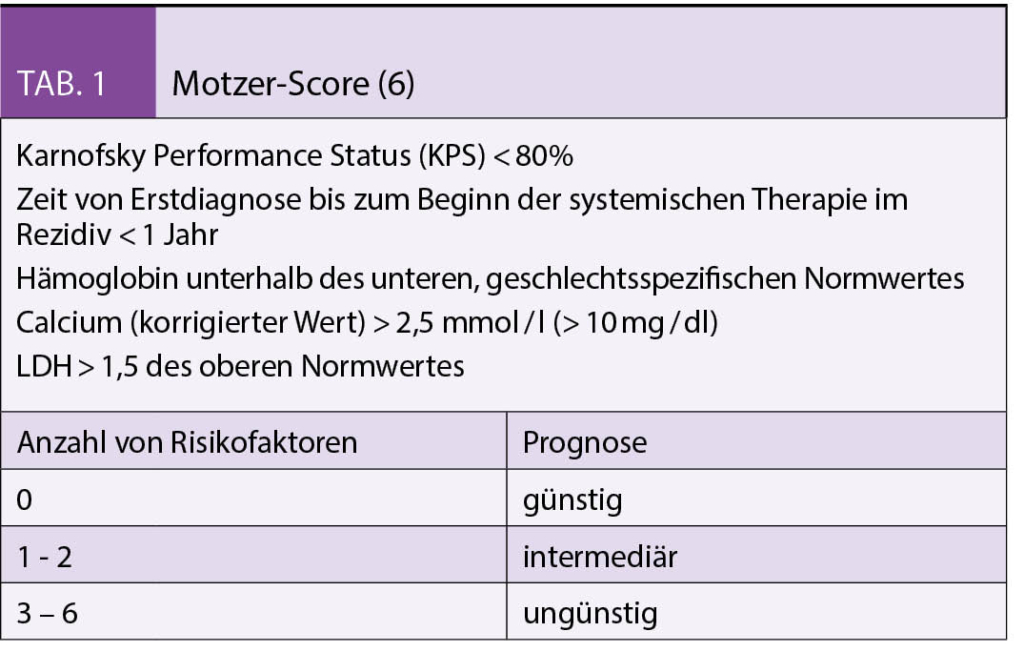

Risikofaktoren des metastasierten Nierenzellkarzinoms

Die metastasierten Tumorstadien werden in die Risikogruppen niedriges, intermediäres und hohes Risiko anhand definierter prognostischer Faktoren eingeteilt. Jedem Risikofaktor wird ein Punkt gegeben. Neben dem Motzer-Score (Tab. 1) wird aktuell vorwiegend der International Metastatic Renal-Cell Carcinoma Database Consortium (IMDC) (Tab. 2) Score zur Einteilung angewendet (6-7).